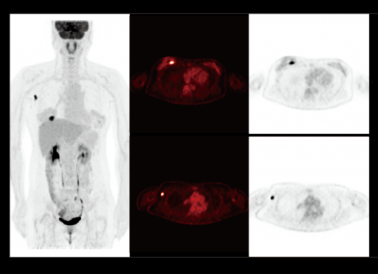

原理先容:PET显像关于恶性淋巴瘤的诊断迅速度较高,已建议作为恶性淋巴瘤的初始分期、再分期及疗效随访的标准影像手艺

临床用途:PET/CT可以通过「一站式」显像发明全身险些所有被侵占的淋投合和结外器官,临床资料显示,PET/CT对恶性淋巴瘤分期的准确性较高